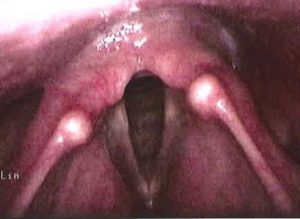

Figure 2. Larynx after reflux treatment

Figure 4. Dramatic healing of larynx after whole foods, plant based nutrition plan instituted in the same patient without medications